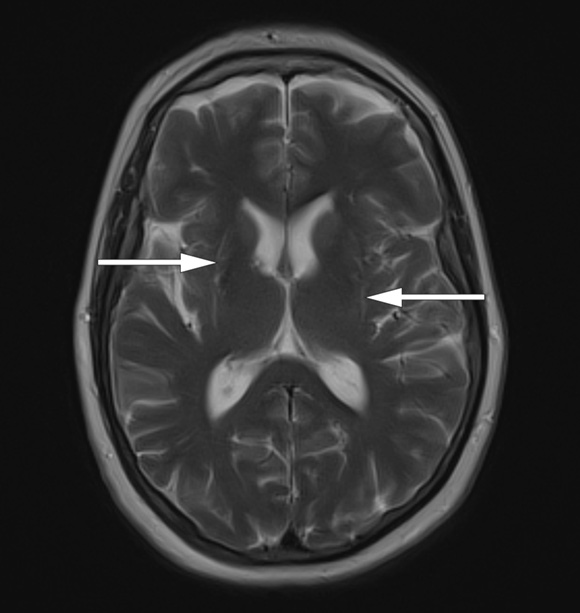

Ved undersøkelse var det rigiditet i alle ekstremiteter. Primitive reflekser var til stede, som tegn på skade av hjernebarken. Videoen viser resten av den nevrologiske undersøkelsen med bruk av Unified Parkinson’s Disease Rating Scale. Hennes antecollis med nakkefleksjon på 70 grader vises i starten og mot slutten av videoen. Hun var mimikkfattig og hadde uregelmessig og stillingsavhengig tremor (jerky tremor) i høyre tredje finger. Motorisk tempo var moderat redusert, med tendens til trettbarhet bilateralt. Det var upåfallende gange og fottramping. MR av hjernen med T2-vektede sekvenser viste en brem med høyt signal lateralt i putamen (piler) med symmetrisk volumreduksjon av putamen bilateralt (bildet).

Pasientens uttalte antecollis, uten fleksjonsstilling ellers i ryggsøylen, er et karakteristisk «rødt flagg» som tyder på multippel systematrofi (MSA), spesielt når dette kommer tidlig i sykdomsforløpet (1). Rask utvikling av symmetrisk parkinsonisme og manglende levodoparespons taler for parkinsonistisk multippel systematrofi (MSA-p) (2). Høy signalintensitet på MR-bilde i putamen med atrofi av putamen er nevroradiologiske tegn med høy spesifisitet og støtter diagnosen MSA-p (2). Dysautonomi med vannlatingsforstyrrelser tidlig i forløpet er et av kriteriene for å stille diagnosen «sannsynlig multippel systematrofi» (2).